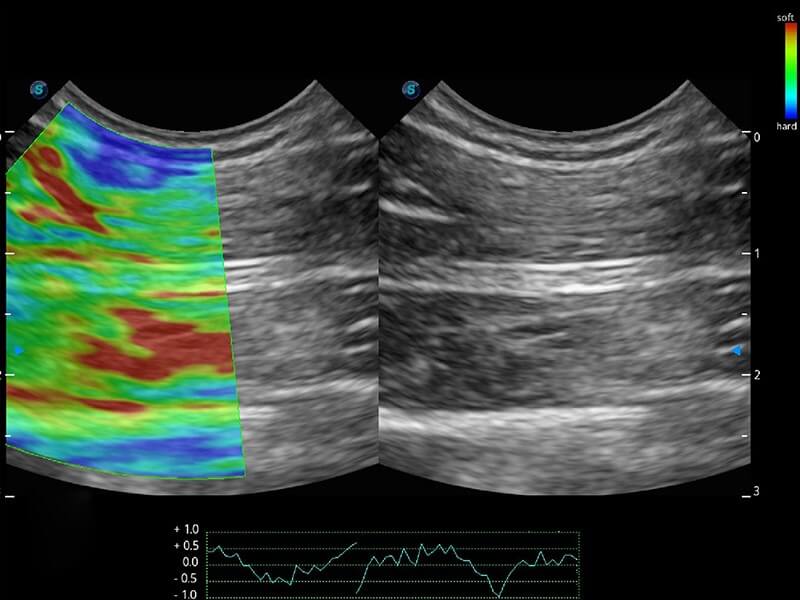

ProPet 60 作为一款高端台式动物超声设备,为动物医生的日常诊断提供了一系列贴合动物临床需求、解决临床实际问题的高级成像功能。凭借全系列高清探头,满足医生对腹部、心脏、生殖、浅表、肌骨等成像的所有需求,切实帮助您提升检查效率,提高诊断信心。